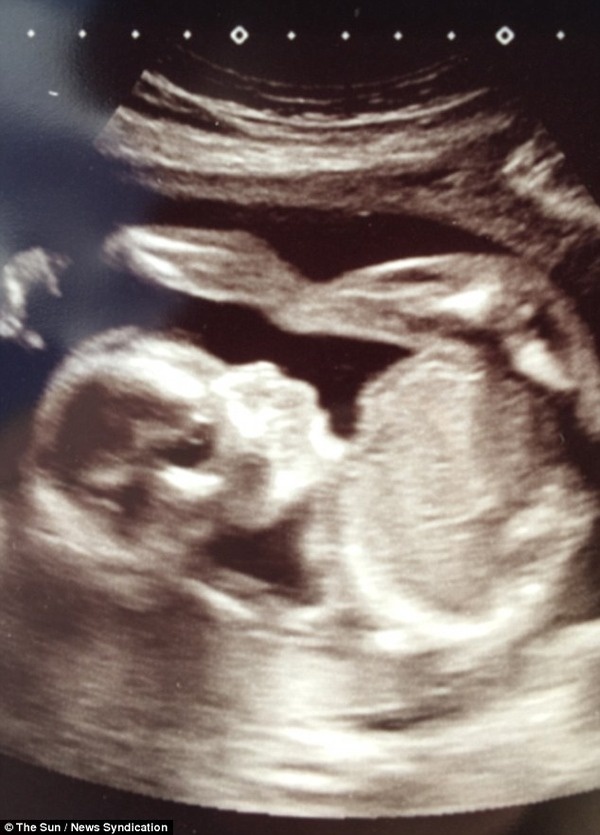

こちらが今回話題となっているお母様「シャーロットバグリー」さん。子供様が20週間に達してとても大喜びということで、エコー写真を見たようです。ところがその写真がとんでもないことになっており大ショック!可愛くない?いやいやそれどころじゃない!とてつもなく「不気味」ということです。赤ちゃんが不気味?どういうことでしょう。

こ!これは・・・かなり不気味な顔ですが確かにこれは

もちろんこれはエコーなので、本物とは違うしそもそも顔じゃないのでご安心してくれれば良いのですが、その前にこんな死神のような不気味な映像が赤ちゃんに取り憑いていたら。想像以上に恐ろしいでしょうね。